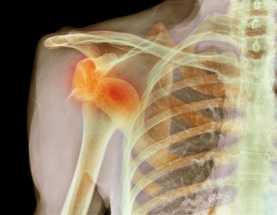

При такой патологической ситуации, как вывих головки плечевой кости, её поверхности полностью утрачивают контакт с поверхностями лопаточной кости. При этом под действием сместившихся костей может отмечаться разрыв суставной сумки и связочного аппарата в соответствующей области.

Рентген в двух проекциях (прямой и осевой) довольно чётко может показать отклонение текущего состояния плечевого сустава от нормы. На снимках можно увидеть, насколько смещена головка плечевой кости, каково направление её смещения, а также наличие переломов костей (если они есть). С помощью рентгена можно определить тип вывиха и предположить развитие возможных осложнений. Не допускается вправлять вывих без предварительного проведения рентгена.

Проведя рентгенографию костей плеча, можно обнаружить подвывих. Это состояние схожее с вывихом, но контакт между поверхностями лопаточной и плечевой кости утрачивается не полностью, а частично.